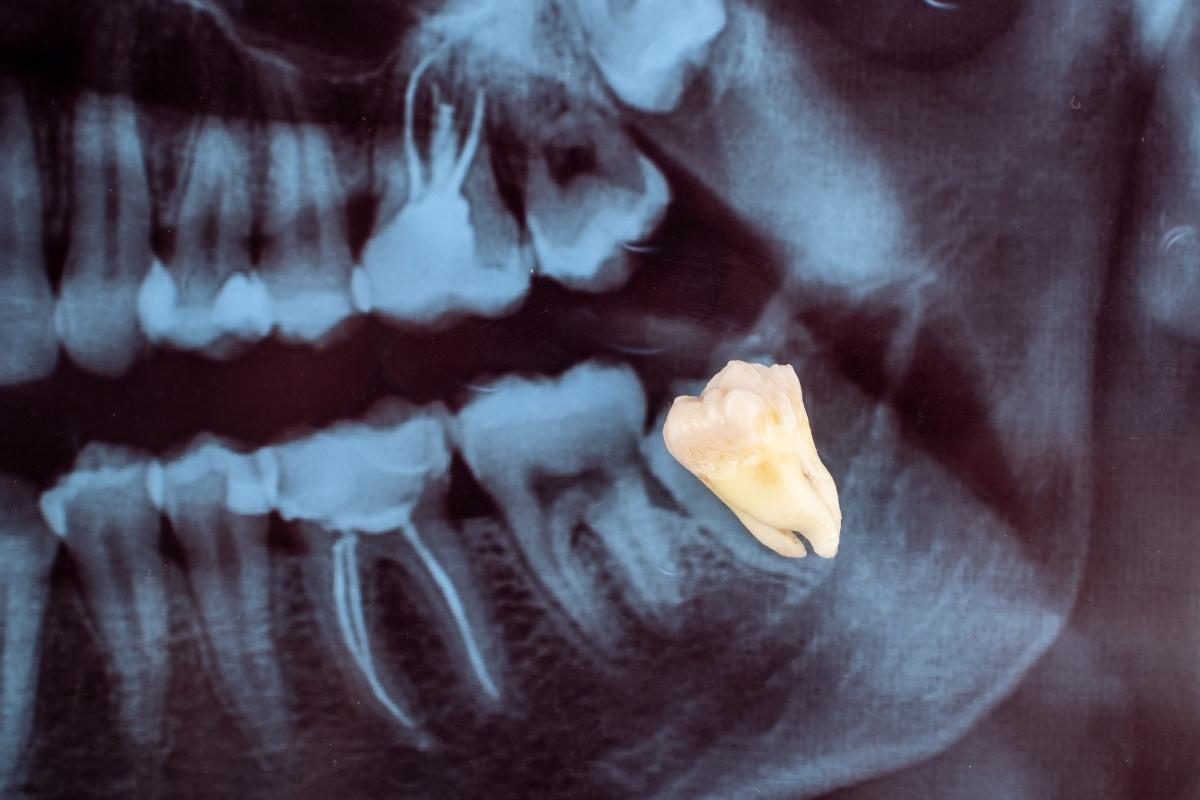

1. Muayene ve Görüntüleme

İlk olarak panoramik röntgen veya 3 boyutlu dental tomografi (CBCT) ile dişin konumu, kök yapısı ve sinirlerle olan ilişkisi değerlendirilir.